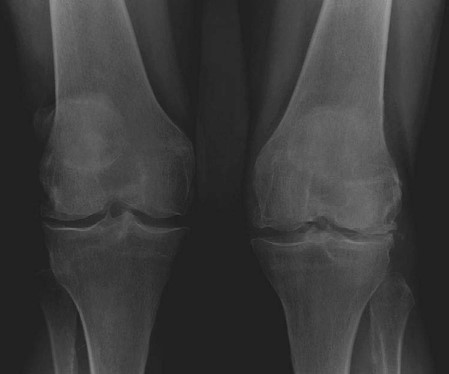

EXAMINER : This is a radiograph of a 72-year-old lady complaining of pain and gradual deformity of both knees. She has been referred to your clinic to be considered for total knee arthroplasty. What can you see? (Figure 3.1.) CANDIDATE : These are weightbearing anteroposterior ( AP ) views of a 72-year-old lady demonstrating narrowing of joint spaces with bone-on-bone contact in the lateral compartments of both knees. There is early arthrosis affecting the medial compartments of both knees. There is moderate valgus deformity. EXAMINER : What conditions are associated with this pattern of joint disease? CANDIDATE : The valgus deformity of the knee with arthritis is commonly seen in women and in inflammatory joint conditions such as rheumatoid arthritis. It can also occur in primary osteoarthritis, overcorrection of high tibial osteotomy (HTO), post-traumatic arthritis following lateral meniscectomy and osteonecrosis. EXAMINER : What are the perioperative considerations for total knee arthroplasty in valgus knee? CANDIDATE : The preoperative assessment should include a thorough history and examination to establish if there are any predisposing factors such as rheumatoid arthritis and the success of non-surgical management. The competency of the knee collateral ligaments and degree of deformity correction should be assessed in order to plan on type of implants. I would use a medial parapatellar because this gives good access to the whole knee and better soft tissue cover. I am aware that a lateral approach can also be used. EXAMINER : What is the theoretical advantage of a lateral approach? CANDIDATE : It is a direct approach providing easier access and preserves the neurovascular supply to the extensor mechanism. EXAMINER : Tell me more about the intraoperative considerations. CANDIDATE : In valgus knees the lateral femoral condyle is deficient, therefore the femur is internally rotated and tibia is externally rotated. The medial structures are stretched while lateral and posterior structures are contracted. The vastus lateralis acts as a subluxing or dislocating force to the patella. In mild valgus deformity (7โ10) a distal femoral cut of 7 can improve patella tracking and avoid the need for lateral retinacular release. Due to the posterior femoral condyle deficiency, the standard 3 posterior condylar referencing can result in internal rotation of the component. In this situation,

Figure 3.1 Anteroposterior (AP) radiograph bilateral knees.